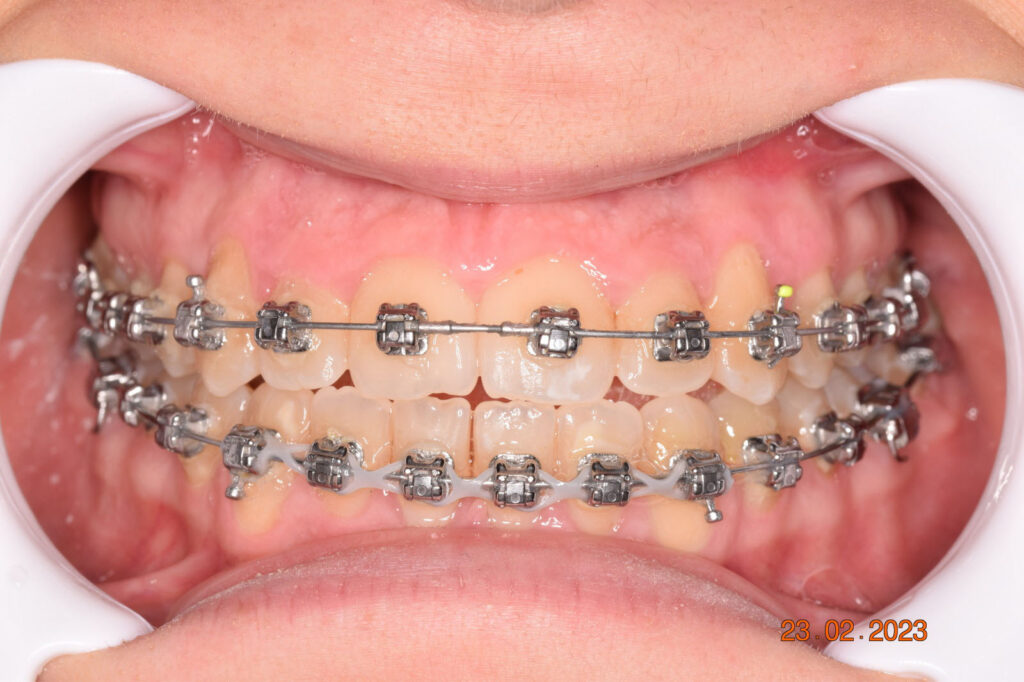

The results were unsatisfactory and the patient began losing interest in the treatment. Dr. Coca and the patient agreed to extend the treatment for six more months and then stop, regardless of the outcome.

The teeth are in a very good position and the bone has reshaped.